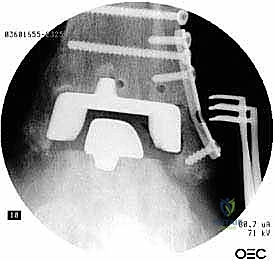

مراجعة مفصل الكاحل الصناعي هي إجراء جراحي ضروري لمعالجة المشاكل التي قد تنشأ بعد الجراحة الأولية، مثل كسور الكعبين أو عدم استقرار المفصل. يتضمن العلاج التشخيص الدقيق عبر الأشعة السينية والتصوير المقطعي، يليه التدخل الجراحي لتثبيت الكسور واستعادة وظيفة الكاحل، مع التركيز على التعافي المبكر.

تُعد جراحة مراجعة مفصل الكاحل الصناعي (Revision Total Ankle Replacement) من الإجراءات الجراحية المتقدمة والبالغة الدقة في عالم جراحة العظام الحديثة. لا تقتصر هذه الجراحة على مجرد استبدال مفصل تالف بآخر جديد، بل هي عملية إنقاذ معقدة للغاية تهدف إلى معالجة المشاكل الميكانيكية والبيولوجية التي تنشأ بعد الجراحة الأولية. من أبرز هذه المشاكل: الفشل الميكانيكي للمفصل، تحلل العظام (Osteolysis)، أو حدوث كسور معقدة في الكعبين (Malleolar Fractures) المحيطة بالمفصل الصناعي. يتطلب هذا الإجراء تقييماً سريرياً وشعاعياً دقيقاً يشمل التصوير المقطعي ثلاثي الأبعاد والأشعة السينية، يليه تدخل جراحي دقيق لاستعادة التوازن الحيوي والميكانيكي للكاحل والحفاظ على الطرف من البتر أو الدمج.

- الأشعة السينية مع تحميل الوزن (Weight-bearing X-rays): لتقييم الزوايا الميكانيكية وتحديد مدى هبوط المفصل أو وجود كسور في الكعب.

- التصوير المقطعي المحوسب (CT Scan): وهو الأداة الذهبية لتقييم "المخزون العظمي" (Bone Stock). يوضح بدقة حجم الأكياس العظمية ومقدار العظم المفقود الذي سيحتاج لترقيع.

تعتبر غرفة العمليات ساحة لإظهار البراعة الجراحية. عملية المراجعة تستغرق عادة من 3 إلى 5 ساعات وتتم عبر الخطوات المعقدة التالية:

الخطوة الخامسة: تركيب المفصل الجديد أو الدمج

يتم إدخال المفصل الجديد المخصص للمراجعة، والذي يحتوي غالباً على سيقان (Stems) تدخل عميقاً في عظمة الساق وعظمة الكاحل لضمان الثبات الميكانيكي. في حال وجود كسور في الكعب، يتم تثبيتها في هذه المرحلة.